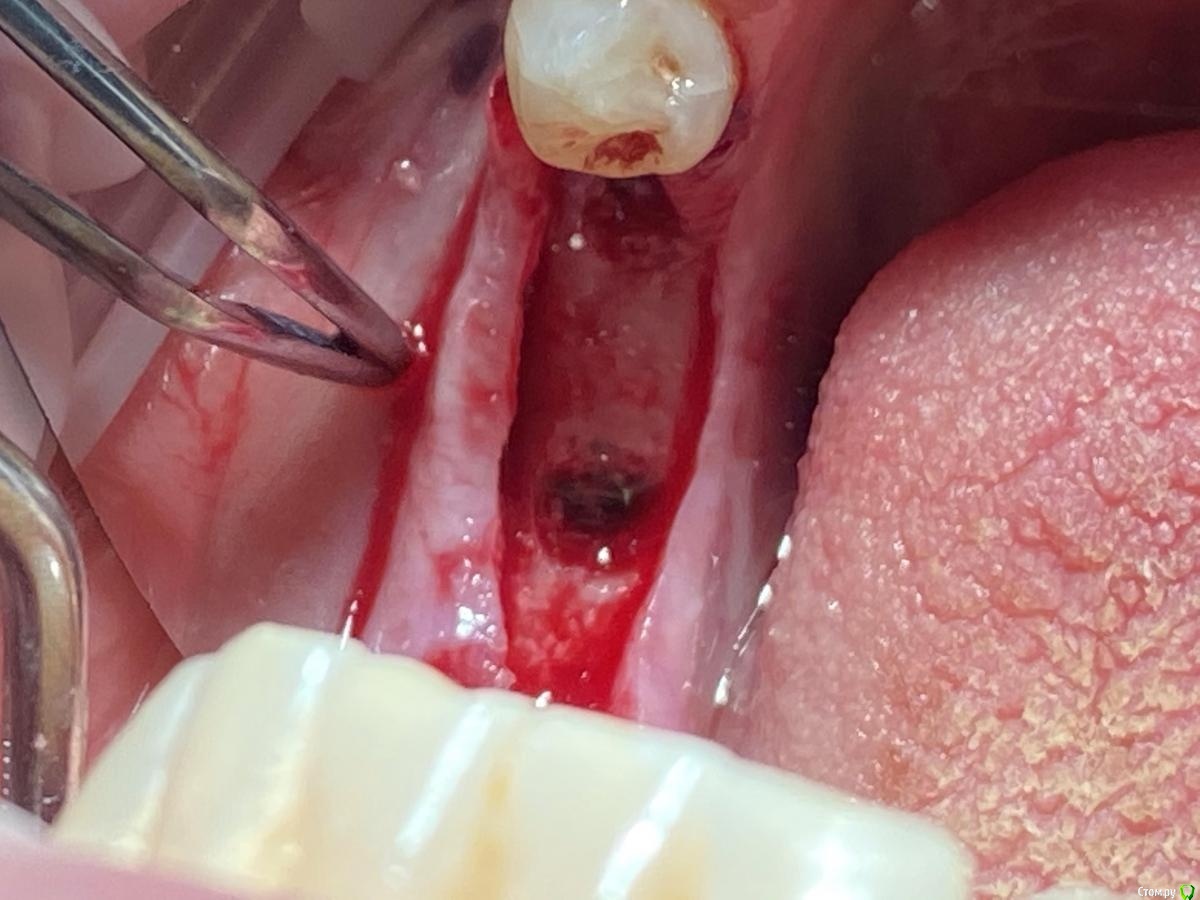

Женька Опубликовано 28 ноября, 2020 Поделиться Опубликовано 28 ноября, 2020 (изменено) Приветствую коллеги. В общем три недели назад 07.11.20 установил пациентке 2 имплантата в позиции 45-46. Гребень по ширине был около 6.5мм в области 4.5 и около 7.2мм в области 4.6 (с учётом заглубления на 1.5-2мм). Это была наверное первая имплантация во время которой я чувствовал себя спокойно и расслабленно. Всё прошло хорошо, немного покопался с непосредственным введением имплантатов, тк никак не хотели топиться на нужные 1.5мм. Поэтому пробовал методику с выкручиванием на пару витков и снова закручиванием. Особого толку не получил, потому взял финальную фрезу и чуть углублял ложе. Так несколько раз, тк боялся всё-таки немного что задену менталис и нлн. Ввиду того, что биотип у пациентки тончайший и язычно было совсем-совсем тонко - заглушки и швы. Назначил нпвс, ванны хг, аб терапию. Но на утро следующего дня пациентка сказала, что чувствует себя шикарно, решили что нпвс оставим, а аб терапию применять не будем (и грешу что в этом мою ошибка).Через неделю сняли швы, всё отлично.Спустя два дня после снятия начались какие-то "костные" боли, как говорит пациентка в области 4.5 импланта. Которые то отпускают, то снова наплывают. На 4.4 есть дефект твердых тканей (на фото виден), но судя по всему беспокоит не он .Пальпация вестибулярно в проекции 4.5 импланта болезненна, небольшая гиперемия, отёка нет. Гигиену пациентка запустила, тк боялась туда залезать и чистить. Снимки прилагаю первые два от 07.11, два последующих 28.11. Ну и внутри ротовые день операции и сегодняшние числа.Похоже 4.5 на выход? своими "туда-сюда" наверняка я нагрел всё что можно... снова расстройство в той работе, где накосячить предельно сложно... Добавка: пить аб ведь сейчас уже бесполезно? Изменено 28 ноября, 2020 пользователем Женька Ссылка на комментарий

Irouil Опубликовано 28 ноября, 2020 Поделиться Опубликовано 28 ноября, 2020 Почему такая атрофия по линии разреза? Ссылка на комментарий

Женька Опубликовано 28 ноября, 2020 Автор Поделиться Опубликовано 28 ноября, 2020 Почему такая атрофия по линии разреза?Может из-за непрерывного шва? Который Ревердена-Мультановского. Ссылка на комментарий